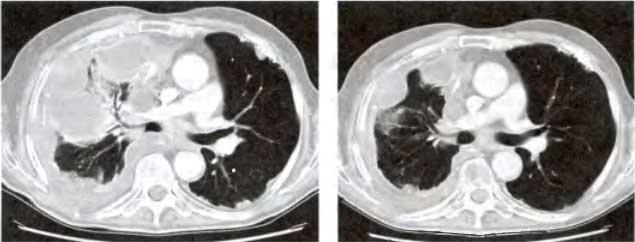

Рис. 24.8. Ингибиторы деаиетилаз гистонов могут вызывать регрессию опухоли

Компьютерные томограммы (СТ) пациента с мезотелиомой (левый снимок) Перед лечением в правом легком наблюдалась большая плоская белая масса, сжимавшая аэрируемую черную часть легкого (см. стрелку). (Правый снимок) Спустя 4 месяца после лечения препаратом SAHA; наблюдается сморщивание опухоли и гораздо более расправленное правое легкое (снимки любезно предоставлены Др. Полом Марксом — Paul Marks, Memorial Sloan-Kettering Cancer Center, NY.)